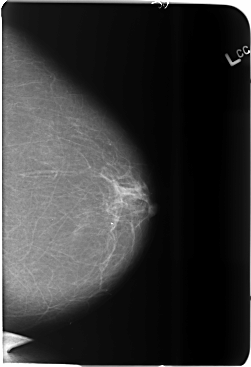

B_3685_1.LEFT_CC

LEFT_CC LINES 5872 PIXELS_PER_LINE 4016 BITS_PER_PIXEL 12 RESOLUTION 50 NON_OVERLAY

LEFT_MLO LINES 5880 PIXELS_PER_LINE 4064 BITS_PER_PIXEL 12 RESOLUTION 50 NON_OVERLAY